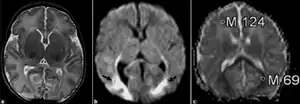

| Neonatal adrenoleukodystrophy a) The axial T2-weighted MR image is normal (b) the diffusion-weighted image (b = 1000 sec/mm2) reveals high-signal changes in the splenium of the corpus callosum, and occipital lobes (black arrows) c) the ADC map reveals that the ADC values of the involved regions is low (0.69 × 10–3 mm2/sec), compared to the frontal regions (1.24 × 10–3 mm2/s). |